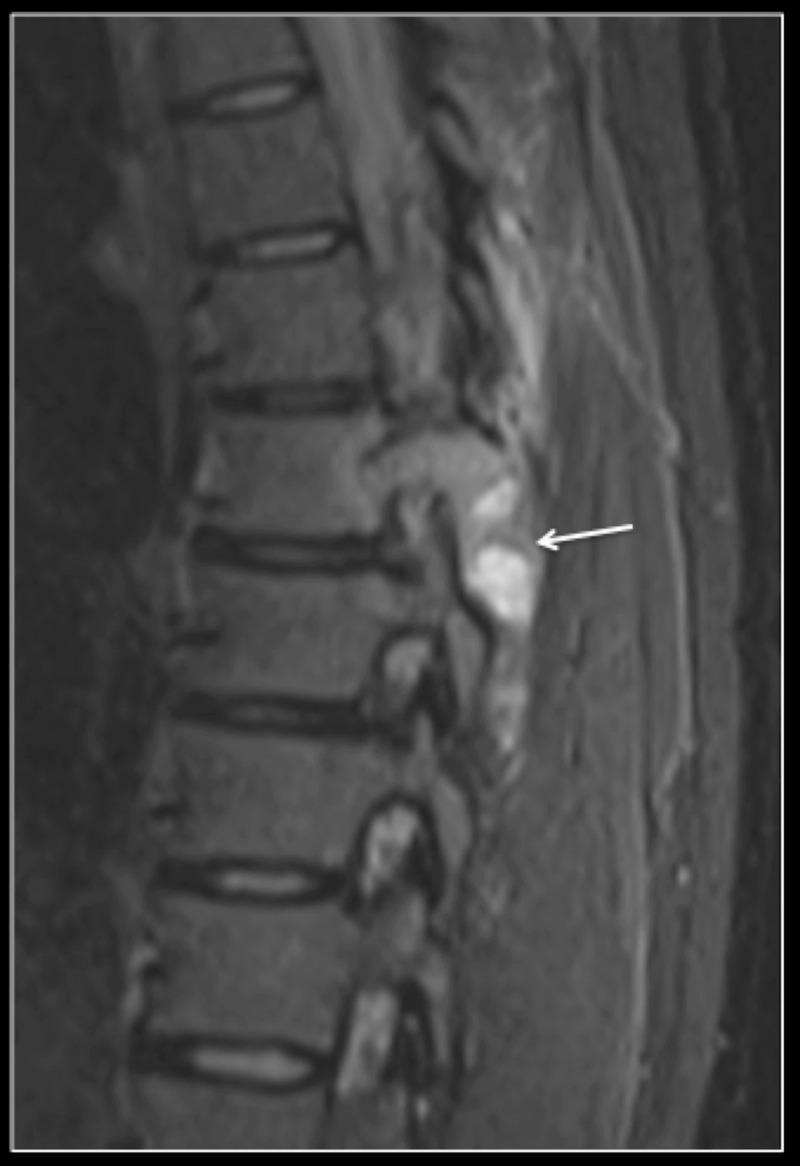

Giant cell tumour (GCT) of the spine is a benign aggressive tumour with high recurrence rates. Patients can be asymptomatic due to the slow growth rate and present with localized pain or neurological dysfunction. Current management strategies include intralesional curettage, total en-bloc resection (TER) and denosumab therapy. Treatment strategies can be particularly challenging in women of childbearing age who wish to conceive, as the risks of tumour recurrence need to be balanced against the fetal complications associated with adjuvant denosumab therapy. This case report discusses the management options and controversies for women of childbearing age with GCT of the thoracic spine. Clinicians need to be aware of the complications associated with TER and denosumab treatment when managing GCTs of the spine in young females.

脊柱巨细胞瘤(GCT)是一种具有高复发率的侵袭性良性肿瘤。由于生长速度缓慢,患者可能无症状,也可能表现为局部疼痛或神经功能障碍。目前的治疗策略包括病灶内刮除术、整块切除术(TER)和地诺单抗治疗。对于希望怀孕的育龄女性,治疗策略可能特别具有挑战性,因为需要在肿瘤复发风险与辅助地诺单抗治疗相关的胎儿并发症之间取得平衡。本病例报告讨论了育龄期胸椎GCT女性的治疗选择和争议。临床医生在处理年轻女性脊柱GCT时,需要了解与TER和地诺单抗治疗相关的并发症。